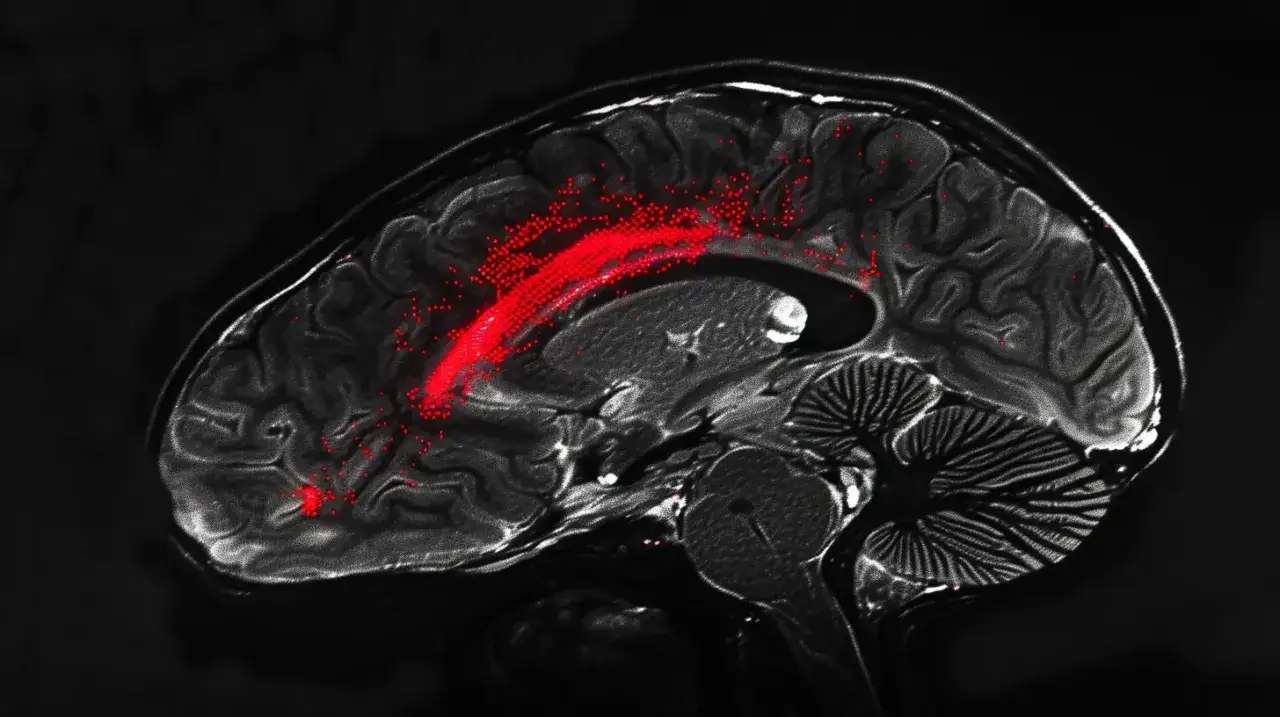

W przypadku guzów mózgu proces diagnostyczny obejmuje bardziej zaawansowane techniki, takie jak badania obrazowe (np. tomografia komputerowa lub rezonans magnetyczny). Te metody pozwalają lekarzom zobaczyć struktury mózgu i zidentyfikować ewentualne nieprawidłowości. Dodatkowo, w niektórych przypadkach może być przeprowadzona biopsja, aby potwierdzić obecność komórek nowotworowych. Wczesne wykrycie guza mózgu jest kluczowe dla skutecznego leczenia, dlatego ważne jest, aby nie ignorować objawów i skonsultować się z lekarzem.